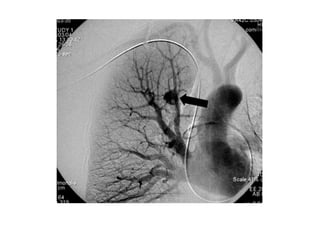

ARTERIOGRAFIA DX

Es obtener el mayor

detalle anatómico

posible de las

estructuras vasculares

que participan en el

sangrado.

Px estable y

examen

dirigido al lado

y sitio de la

lesión detecta

por cualquier

método de

imágenes.

El 1er objetivo

es diagnóstico,

el cateterismo

debe ser con

intención

terapéutica:

embolización.

DEFECTO REPLECION ARTERIAL